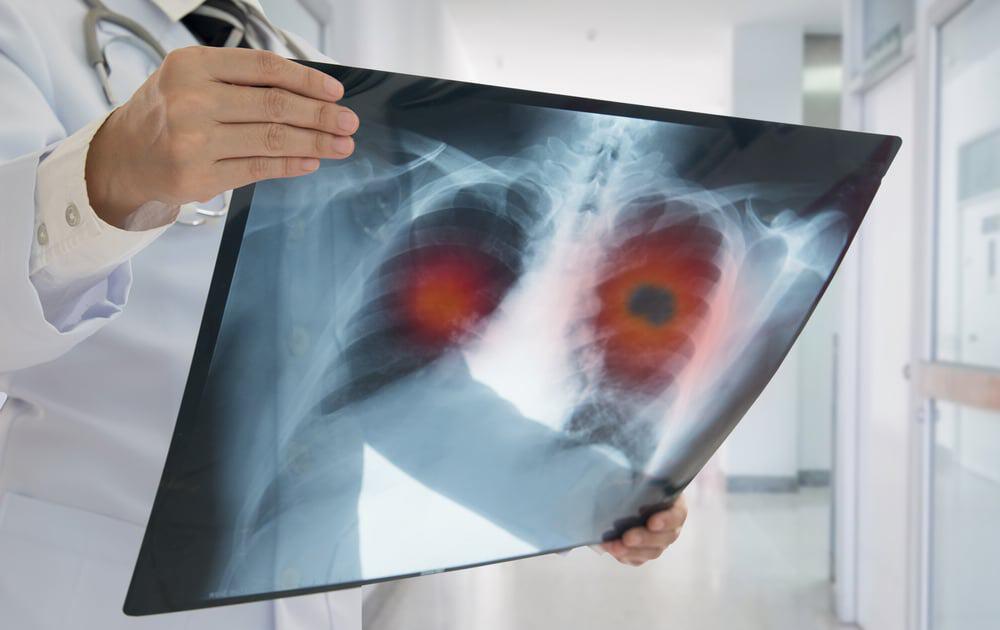

Chẩn đoán

Đầu tiên, bác sĩ sẽ khám các triệu chứng và hỏi về tiền sử bệnh nhân. Sau khi đánh giá lâm sàng, bác sĩ có thể chỉ định một số kỹ thuật cận lâm sàng như:

- Chụp X-quang ngực thẳng hoặc cắt lớp vi tính ngực (CT scan)